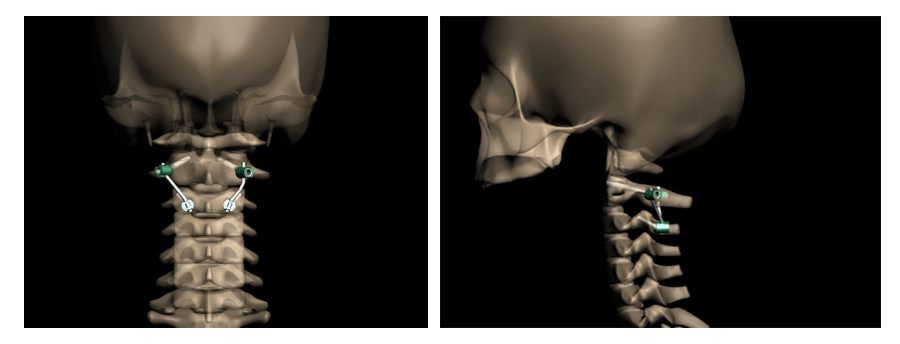

Поэтому специалисты нашей клиники в Санкт-Петербурге считают, что наиболее биомеханически обоснованным и эффективным методом лечения перелома палача является устранение смещения и фиксация ножек С2 с помощью специальной методики транспедикулярной фиксации.

Суть данного способа лечения заключается в том, что ножка С2 крепко соединяется винтом, отломки прижимаются к друг другу за счет специального хирургического приема. Тело С2 подтягивается на место. Данный метод с успехом применяется у нас в клинике и за рубежом уже более 10 лет. Его можно использовать как в экстренных случаях, так и при застарелых повреждениях, даже если пациент находится в иммобилизации воротником несколько месяцев.

Рис.3 Схема репозиции и фиксации позвонков при переломе палача